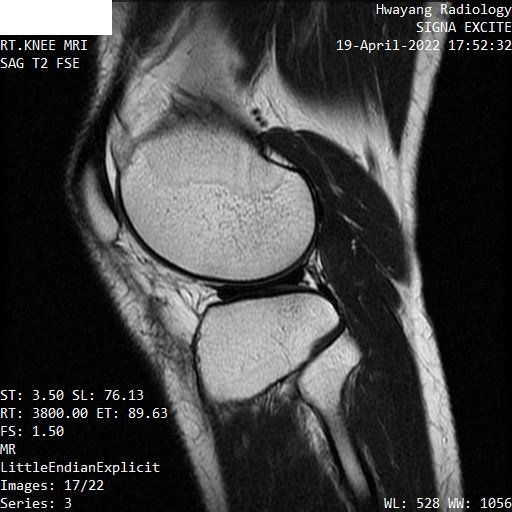

무릎연골 파열 mri좀 봐주세요 파열이 맞는지 궁금합니다.

오른쪽 무릎이 아파서 mri 찍어봤는데 집근처 병원에서 연골파열이라고 하는데

MRI 컷을 위와 같이 배열해놓은 것으로는 명확한 감별이 어렵습니다.

다만 연골부위의 MRI 상 이상 소견이 있는 것은 사실입니다.